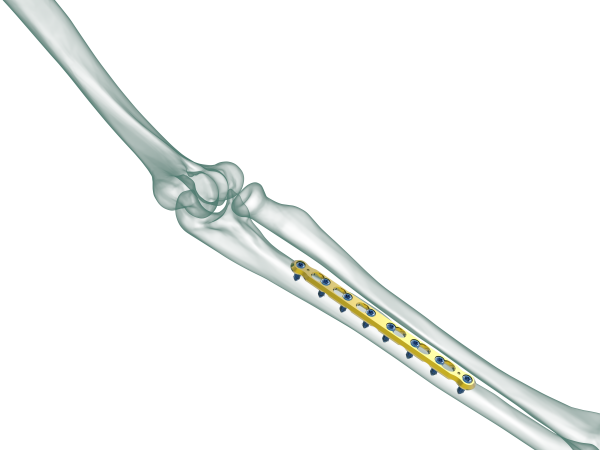

TRUE LOCK 3.5mm Ulna Radius Plate

TRUE LOCK 3.5mm Ulna Radius Plates are indicated for fractures of ulna, radius and fibula shaft.

Radius and ulna body fractures differ from other diaphyseal fractures due to the relationship between both bones and the fractures can affect the elbow and wrist joints. In adulthood, forearm fractures often require surgical treatment, as they are noticeably displaced and unstable.

Low plate-and-screw profile and rounded plate edges minimize potential for tendon and soft tissue irritation.

The combi-hole pro- vides flexibility of axial compression and locking capability throughout the length of the plate shaft.

Images Gallery